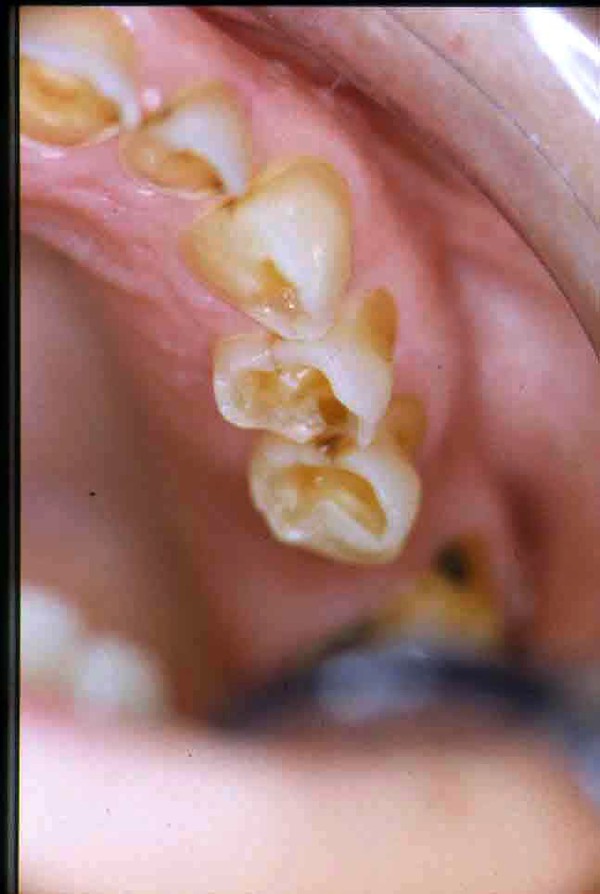

APRECIACIONES DIAGNÓSTICAS EN BASE A LA APERTURA MENTAL DEL CLÍNICO FRENTE A LO QUE EL PACIENTE PROPONE EN MUCHAS OCASIONES , LA DEMANDA DE LOS PACIENTES NOS INCLINAN A FOCALIZAR NUESTRA ATENCIÓN EN LAS PIEZAS DE LAS CUALES EL ENFERMO SE QUEJA. PACIENTE SEXO FEMENINO, 55 AÑOS, SE PRESENTA A LA CONSULTA DERIVADA POR COMPAÑERO GENERALISTA, QUIEN LLEVA MESES PROCEDIENDO A LA «DESINFECCIÓN» DE UN PRIMER PREMOLAR IZQUIERDO, EL QUE SE PRESENTA ABIERTO EN SU CONDUCTO EN EL AFÁN DE PERMITIR EL ESCAPE DE GASES DE UNA GANGRENA PULPAR. A LA INSPECCIÓN CLÍNICA SE OBSERVAN FACETAS PARAFUNCIONALES DE TERCER GRADO , ASINTOMÁTICAS, CON EVIDENTES DIFICULTADES MASTICATORIAS Y ESTÉTICAS , FALTA TOTAL DE SUS MOLARES INFERIORES, Y ADELANTAMIENTO PRONUNCIADO DE SU MANDIBULA, LA QUE CUESTA MANIPULAR DEBIDO A LA SITUACIÓN DE ESPASMO DE CASI TODA SU MUSCULATURA GNATICA. SE ESTUDIA EL CASO RADIOLOGICAMENTE, Y SE RELAJA EL SISTEMA MEDIANTE LAM. DE LONG REALIZANDO UN MONTAJE EN LA ORC OBTENIDA. NO SATISFECHOS CON EL RESULTADO, CONFECCIONAMOS UN JIG DE LUCIA, EL QUE DEJAMOS EN BOCA TODA UNA NOCHE, AL CABO DE LA CUAL REALIZAMOS UN NUEVO REGISTRO REALIZAMOS UN ENCERADO RÁPIDO DEL CASO, Y CONFECCIONAMOS UNA ESTRUCTURA OCLUSAL PLASTICA, QUE ADEMÁS REPONGA EL ASPECTO ESTÉTICO PERDIDO (FÉRULA DE RELAJACIÓN DE COMPONENTE ESTÉTICO), LO QUE PERMITE AL ENFERMO LUEGO DE DOS DÍAS DE USO, NO SOLO CORROBORAR LA COMODIDAD MASTICATORIA Y LA FALTA DE SÍNTOMAS MUSCULARES, SINO TAMBIÉN OBSERVAR APROXIMADAMENTE LA DIFERENCIA ENTRE LA SITUACIÓN INICIAL Y LO QUE PUEDE LOGRARSE MEDIANTE EL TRATAMIENTO. EL PACIENTE ADVIERTE LA MEJORÍA DE LA SITUACIÓN. ACEPTADO POR PARTE DEL MISMO EL TRATAMIENTO SUGERIDO, CREAMOS UN JUEGO COMPLETO DE PROVISORIOS EN BASE AL ENCERADO, Y PROCEDEMOS A TRATAR LA INFRAESTRUCTURA, QUE CONSISTE EN LAS ENDODONCIAS, SUS REFUERZOS A PERNOS DE ORO, LOS ASPECTOS PERIODONTALES DEL CASO, Y DOS IMPLANTES INFERIORES CON TÉCNICA SEMISUMERGIDA ,DE 5 MM DE ANCHO POR 12 DE LONGITUD, CON ANILLO DE ZIRCONIO , A LA ESPERA DE OSTEOINTEGRACIÓN, TRANSCURREN TRES MESES EN EL USO DE UNA NUEVA OCLUSIÓN CONSTITUIDA POR LOS PROVISIONALES, SEGÚN EL ENCERADO, QUE SE REALIZÓ SIGUIENDO LOS CÁNONES DE UNA OCLUSIÓN ORGÁNICA. COMPROBADA LA EFICACIA DE LA NUEVA SITUACIÓN, CON SUS DISCLUSIONES LATERALES Y POSTERO ANTERIORES CORRECTAS, CARECIENDO YA DE SINTOMATOLOGÍA MUSCULAR (SIN MIALGIAS, SIN MIOSITIS, Y CON UN GRADO DE APERTURA DE 4,50 CM), Y SIN SIGNOS EVIDENTES DE DESGASTE SOBRE EL MATERIAL DE LOS PROVISORIOS, ES DECIR: VERIFICANDO QUE EL PACIENTE YA NO BRUXA, VERTICALIZANDO EL CICLO MASTICATORIO /OTORGANDO ORC/ DIMENSIÓN VERTICAL /PROTEGIENDO A LAS PIEZAS `POSTERIORES DE IMPACTOS LATERALES RECIEN ENTONCES , MONTAMOS EN ARTICULADOR SEMI AJUSTABLE LOS MODELOS DE TRABAJO DEFINITIVOS. CONFECCIONAMOS ENTONCES LAS COFIAS INFRA PORCELANA, EN PORCELANA DE ALTA DENSIDAD EN EL SECTOR ANTERIOR Y EN ORO GALVÁNICO PARA EL SECTOR POSTERIOR PARA LUEGO COMPLETAR LA GUIA ANTERIOR , VERIFICANDO LA ALTURA DE LOS INFERIORES RESPECTO DEL LABIO INFERIOR Y CORROBORANDO LOS PUNTOS DE CONTACTOS INTER CANINOS, QUE CENTRALIZAN LA MANDIBULA Y VERTICALIZAN EL CICLO MASTICATORIO Y LAS DISCLUSIONES CANINAS QUE OTORGARÁN PROTECCIÓN A LOS SECTORES POSTERIORES. POSTERIORMENTE CHEQUEAMOS LA DISCLUSIÓN EN PROPULSIVA DE LA GUIA ANTERIOR YA TERMINADA. FIG38 FIG39 UNA VEZ OBTENIDO UN COMANDO ANTERIOR EFECTIVO, COMO LO ES LA GUIA ANTERIOR CON TODOS SUS COMPONENTES, PROCEDEMOS A REALIZAR LAS TABLAS PREMOLAR / MOLAR DE AMBOS LADOS Y OBSERVAMOS QUE LOS PUNTOS INTEROCLUSALES DE CONTACTO SEAN SUFICIENTES Y CUMPLAN SU OBJETIVO DE OTORGAR ESTABILIDAD MESIO DISTAL Y VESTÍBULO LINGUAL. TRANSCURRIDO UN AÑO DE FINALIZADO EL TRATAMIENTO, REALIZAMOS UN CHEQUEO POST OPERATORIO DEL CASO, EN TODOS LOS PARÁMETROS ANTERIORMENTE MENCIONADOS, Y OBSERVAMOS LA ABSOLUTA ESTABILIDAD DEL MISMO EN TODOS SUS NIVELES Y TEJIDOS.